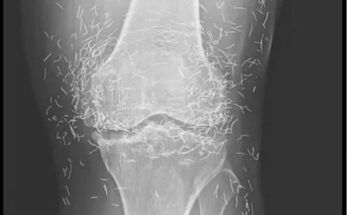

“Hundreds of Gold Needles Discovered in Woman’s Knees After Routine Arthritis Acupuncture—X-Ray Reveals Alarming Reality”

When a 65-year-old woman went in for an X-ray to uncover the cause of her unrelenting knee pain, doctors expected to see signs of arthritis. What they found instead left …